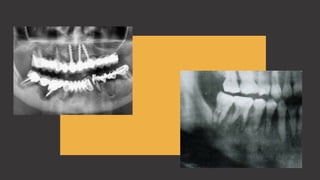

R a d i o l o g í a

A menos que el proceso inflamatorio

dure más de una semana, la evidencia

radiográfica suele estar ausente. Con

el tiempo, comienzan a aparecer focos

radiotransparentes difusos.

Suelen observarse como islotes de

hueso muerto (secuestros), no

reabsorbido, que estan rodeados por

zomas amplias de exudado purulentos.

Se presenta principalmente como una

lesión radiotransparente que algunas

veces evidencia zonas focales de

opacificación.

El patrón de transparencia tiene un

aspecto moteado. Suelen ser lesiones

muy extensa y no es raro que los

bordes sean indistinguibles.